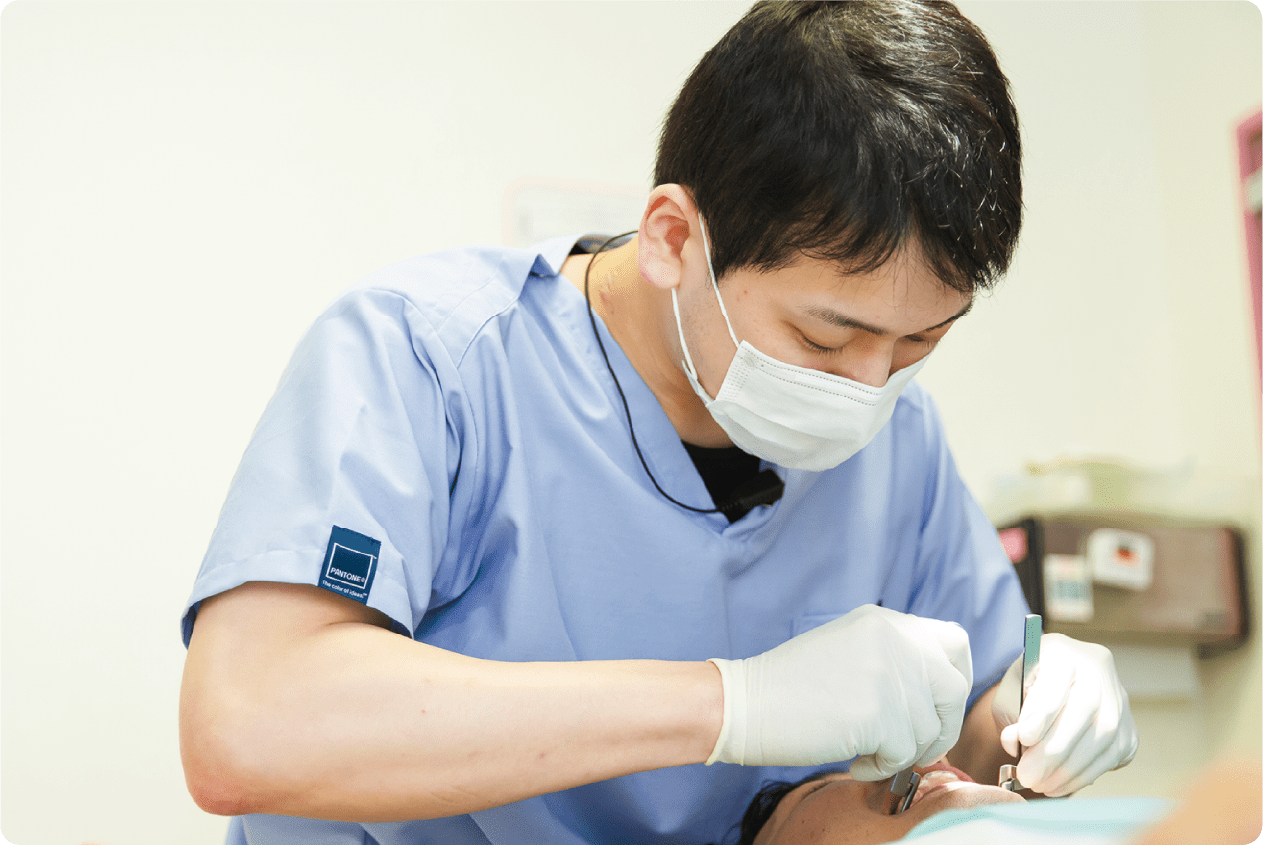

痛くない・なるべく抜かない・削らない治療を基本として、新しい技術を常に学び、大切な歯をお守りします。歯医者さんに行きたいと思ってもらえるように日々奮闘!

初診時はしっかり時間をとります!